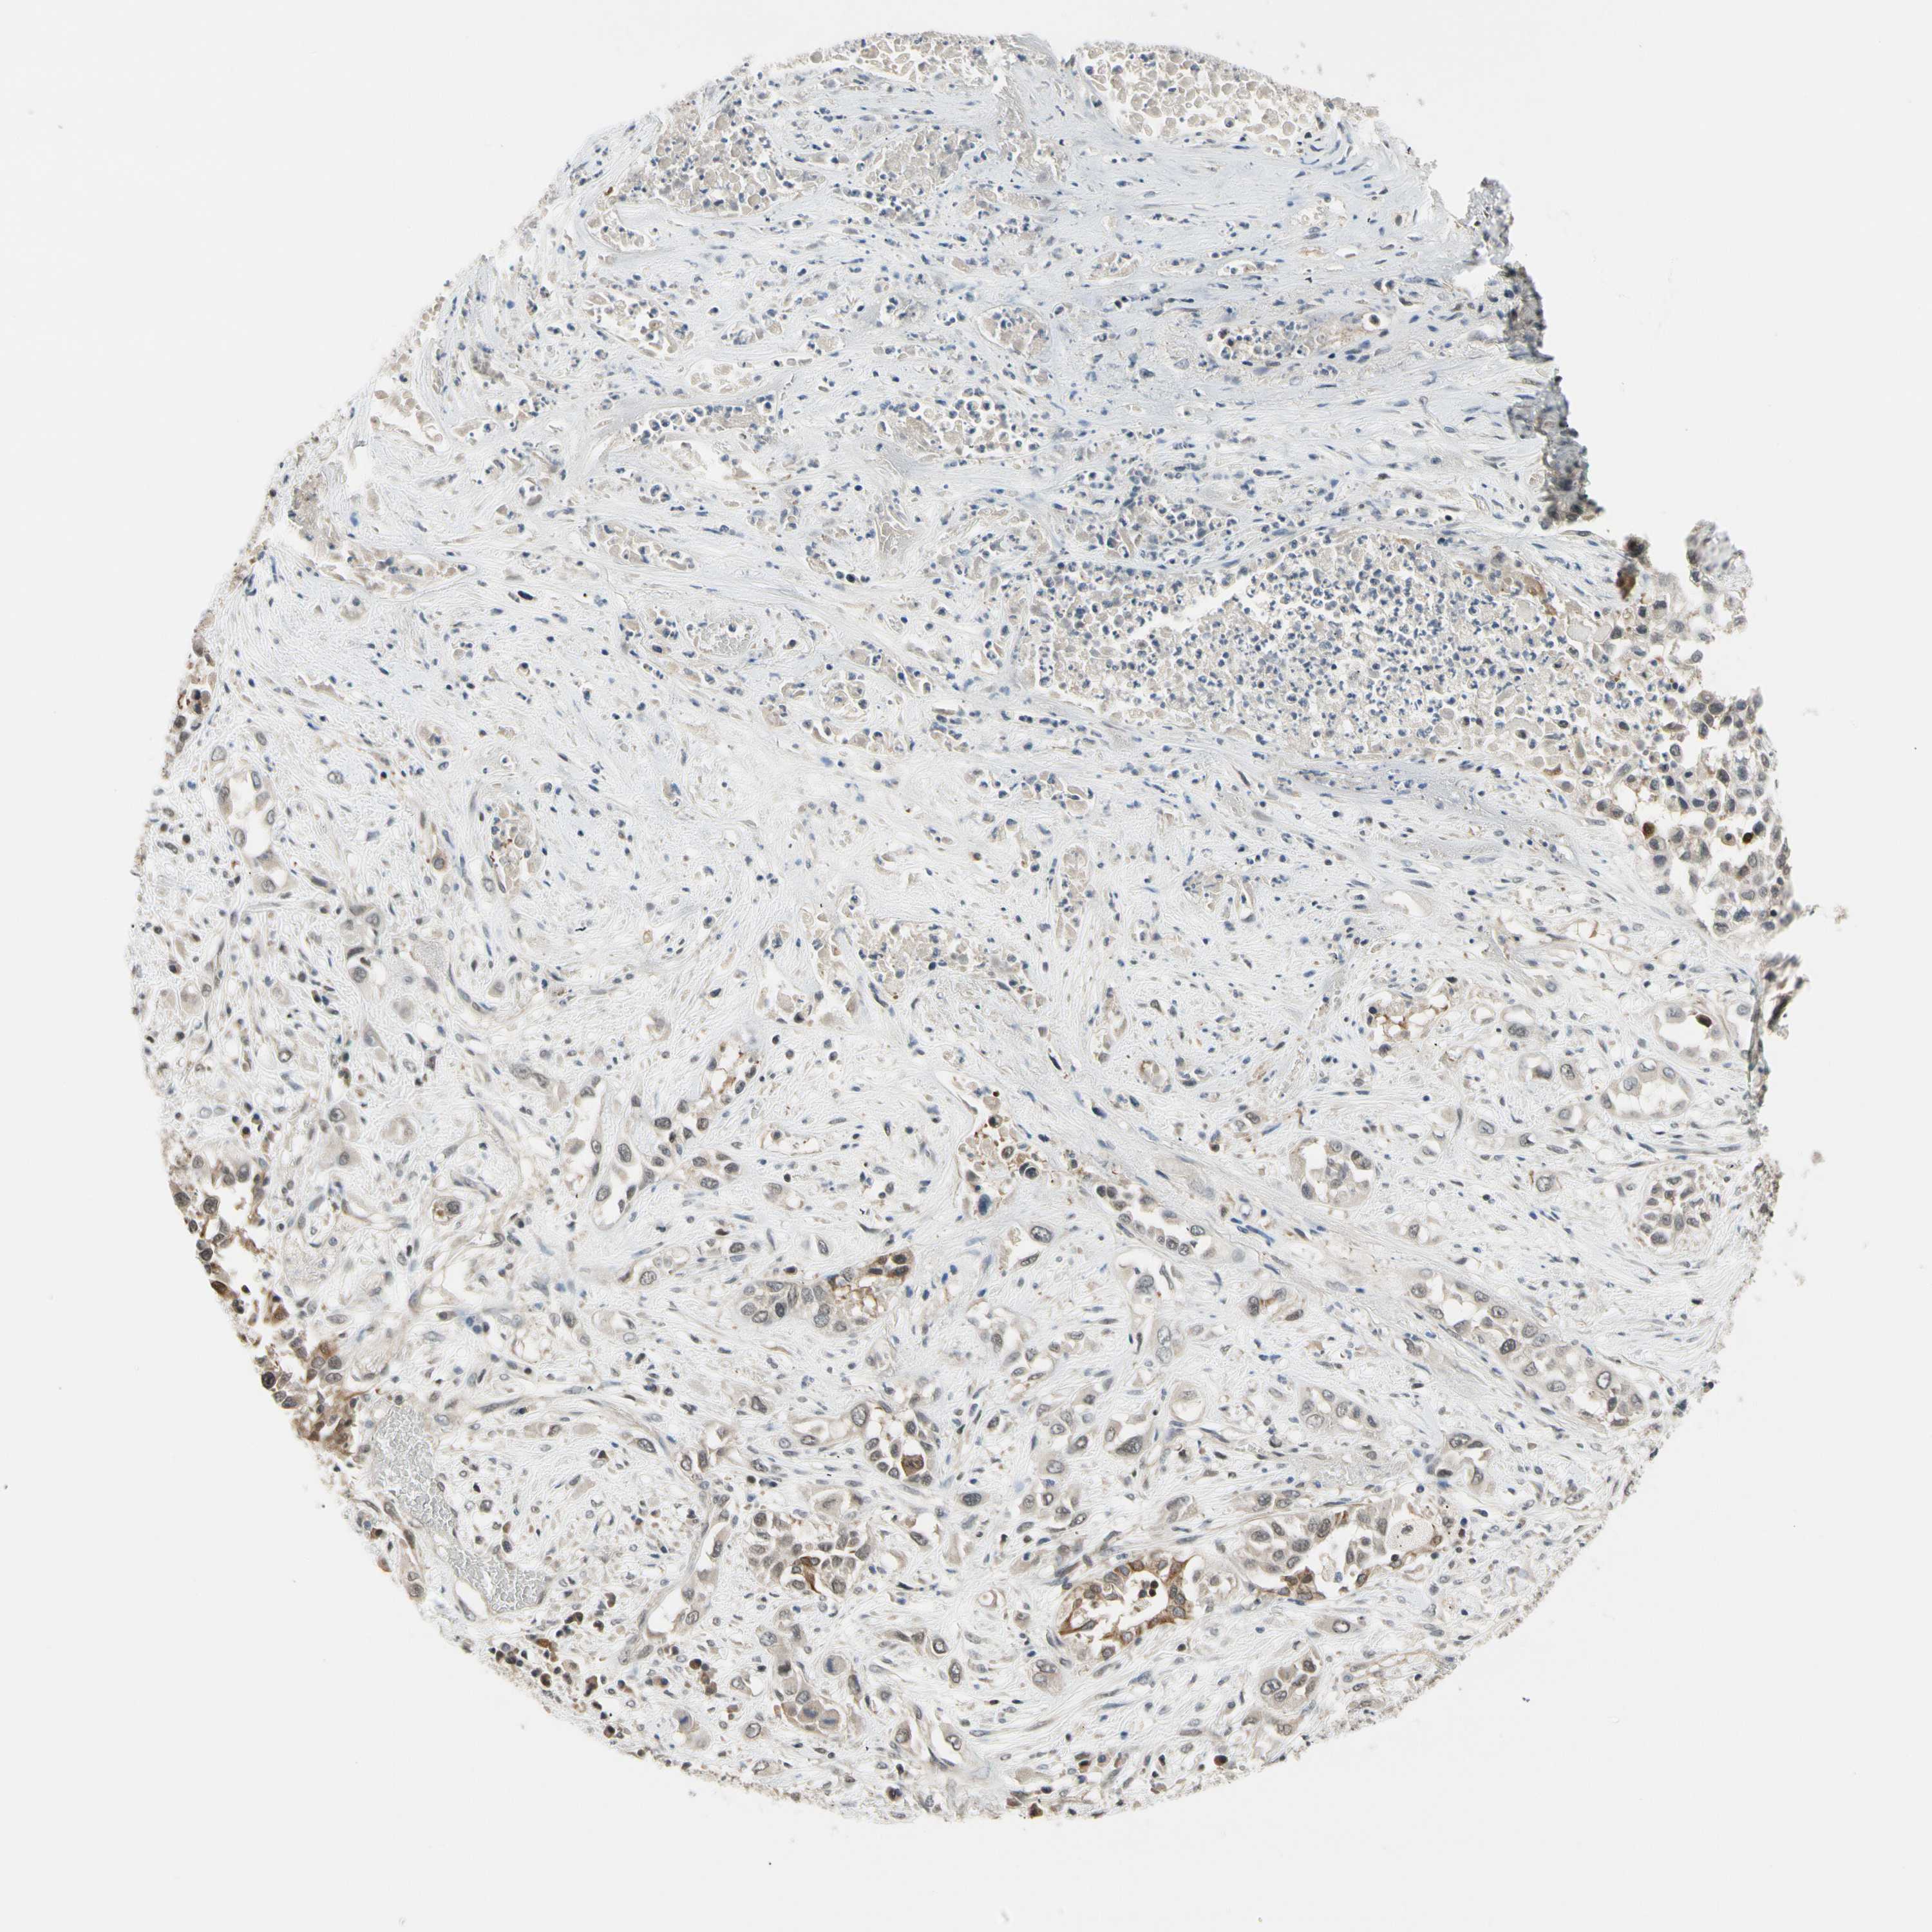

CANCER LUNG CANCER Show tissue menu

LUAD TCGA LUAD VALIDATION LUSC TCGA LUSC VALIDATION PROTEIN LUAD CPTAC PROTEIN LUSC CPTAC PROTEIN EXPRESSION

ANTIBODIES

AND

VALIDATION